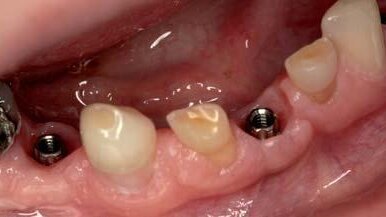

Ze względu na aspekty etyczno-prawne zdecydowano się na zastosowanie leczenia chirurgicznego po osiągnięciu przez pacjentkę pełnoletności. W badaniu zewnątrzustnym stwierdzono zęby stałe:16, 13, 11, 21, 23, 26, 36, 32, 46 oraz zęby mleczne: 55, 62, 63, 75, 71, 82, 83, 85. Pacjentka użytkowała górną protezę częściową osiadającą, była leczona ortodontycznie poprzez wytworzenie i utrzymanie miejsca na wszczepy po utraconych zębach mlecznych. Celem niniejszej pracy jest wykorzystanie metodologii leczenia implantoprotetycznego u pacjentki z użyciem mikroimplantów o średnicy 2,85 firmy Bredent. Ze względu na wymiar językowo-przedsionkowy wyrostka nie byłoby możliwe wykorzystanie implantów szerszych. Uwzględniając budowę kości w przebiegu dysplazji a także brak danych w piśmiennictwie na ten temat, nie poleca się stosowania procedur augmentacji w celu zwiększenia szerokości wyrostka. W żuchwie zastosowano 4 dwuczęściowe implanty MiniSky w pozycjach: 33, 34, 41, 44. Na czas integracji zastosowano gojenie przezśluzówkowe z wykorzystaniem łączników czasowych (mini1SKY MD-Abutment BioXS) z kompozytem typu flow (Kerr Revolution ). Odbudowa czasowa była wyłączona ze zgryzu. Po standardowym okresie gojenia wszczepu w żuchwie (3 miesiące) wykonano wyciski z poziomu stałego łącznika protetycznego z wykorzystaniem czapek typu Snap A i zastosowano odbudowę protetyczną na implantach za pomocą koron metalowych licowanych porcelaną na implantach 41, 44 i mostu metalowego licowanego porcelaną na implantach 33, 34 z dowieszonym do tyłu punktem.

Planowana odbudowa na implantach miała z założenia nie wykorzystywać zębów mlecznych przetrwałych jako elementów kotwiczących czy też koron ze względu na konieczność

szlifowania i możliwość zwiększenia ruchomości, ponadto zęby te mają częściowo zoobliterowane

jamy. Dlatego nie byłoby możliwe jakiekolwiek leczenie endodontyczne. Części koronowe tych zębów odbudowano kompozytem typu flow (Kerr Revolution).

U pacjentów z niedoborem jakościowym i ilościowym tkanki kostnej w przebiegu chorób o podłożu genetycznym, u których augmentacja kości nie jest wskazana lub może okazać się nieefektywna,

implanty o wąskiej średnicy mogą być z powodzeniem wykorzystywane do odbudowy ciągłości łuku zębowego.